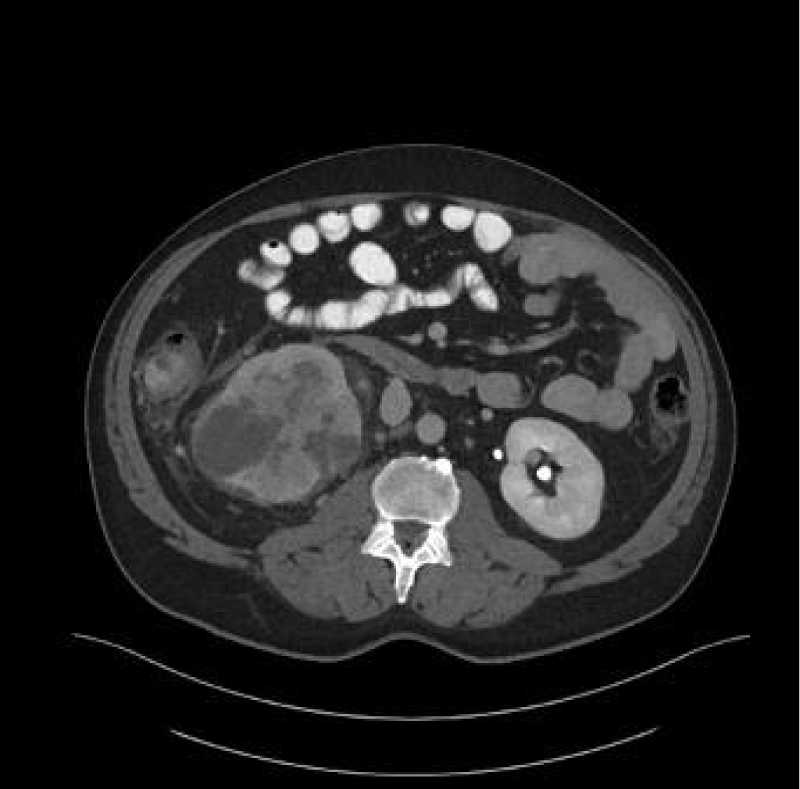

Renal cell carcinoma (RCC) is the ninth and fourteenth most common carcinoma in men and women respectively, alongside being the most lethal urological malignancy. RCC accounts for up to 90% of all kidney cancers, and up to 80% of all SRM. RCC constitutes Clear Cell (Figures 4-6), 75%, Papillary, around 15% to 20%, Chromophobe (Figures 7-9), 5% and other rarer subtypes. Clear Cell is the most common variant with the worst prognosis as it commonly presents at an advanced stage. Papillary type is more frequent in smaller lesion sizes [1,2,3,9-15].

Download Image

Figure 7: Right renal Chromophobe RCC of the lower pole, with solid and cystic components.

Figure 8: Chromophobe RCC of the lower pole of left kidney.

Figure 9: Chromophobe RCC of the lower pole of right kidney.